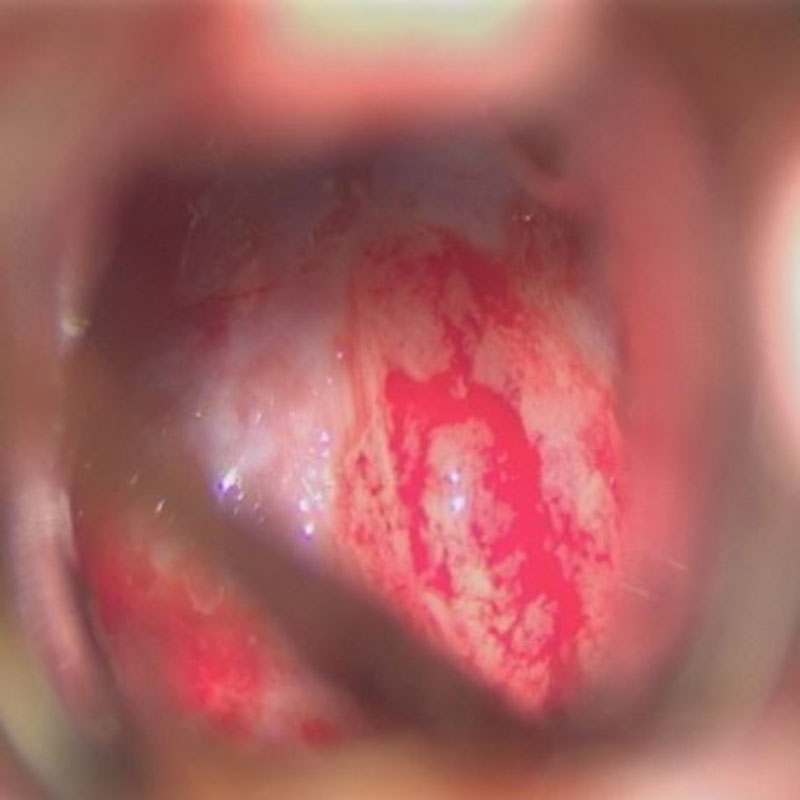

右傍矢状洞髄膜腫

頭蓋内腫瘍摘出術

No.’23_63 摘出 前

No.’23_63  摘出 中

No.’23_63 摘出 後